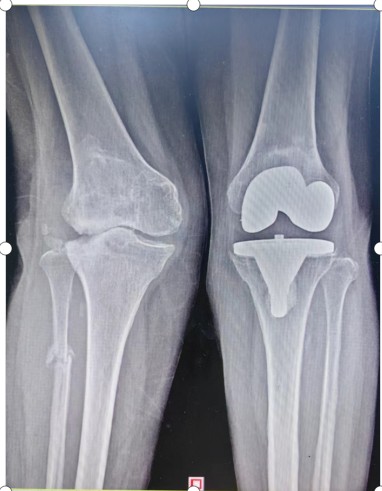

入院后羅湘平主任醫(yī)師、彭健副主任醫(yī)生及蔣瀟純主治醫(yī)師查體時(shí)發(fā)現(xiàn)劉奶奶的右膝關(guān)節(jié)重度外翻,內(nèi)側(cè)副韌帶松弛嚴(yán)重致膝關(guān)節(jié)失去穩(wěn)定性。CT檢查發(fā)現(xiàn)右膝關(guān)節(jié)外側(cè)脛骨平臺(tái)缺損明顯,深度達(dá)1.5厘米以上,長期應(yīng)力異常,導(dǎo)致腓骨近端應(yīng)力性骨折。這種復(fù)雜膝關(guān)節(jié)畸形行人工膝關(guān)節(jié)置換不但技術(shù)難度大,而且費(fèi)用很高。根據(jù)劉奶奶膝關(guān)節(jié)評(píng)估結(jié)果,可能需要行鉸鏈膝關(guān)節(jié)假體及金屬墊塊充填骨缺損,僅假體材料費(fèi)用就要達(dá)6萬余元,普通家庭無法承受。

術(shù)后一年